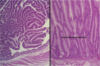

Tubular vs Villous

Tubular Adenoma

Villous Adenoma

Villous Adenoma